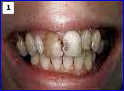

• Restore your smile

Crowns restore natural beauty and health of teeth.